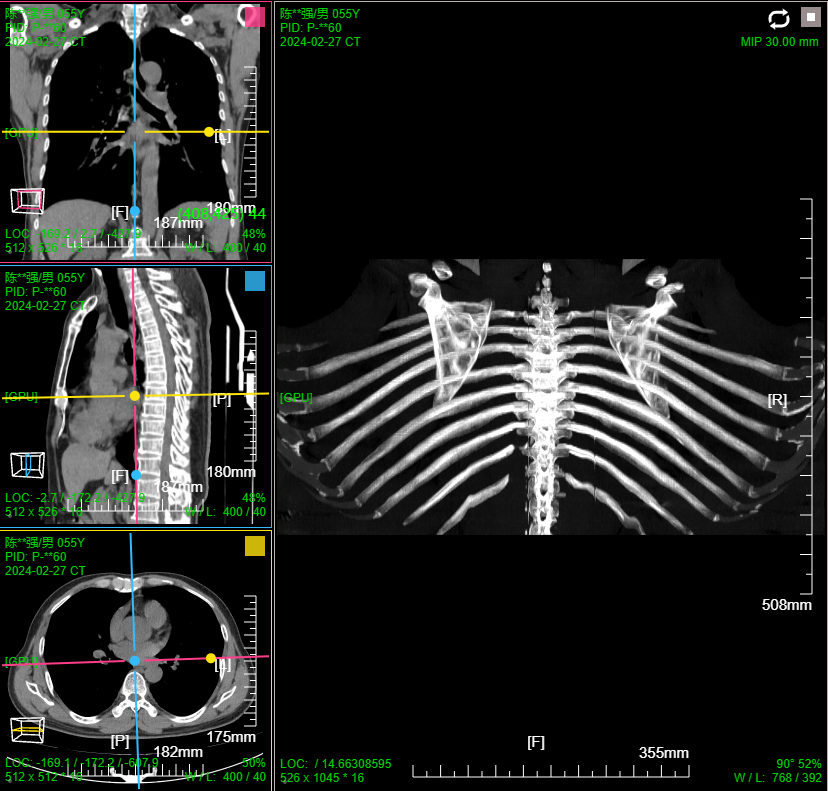

- 支持MPR、CPR、MIP、VR、VE三维图像处理;支持三维裁剪切割 / 一键去床

三维:MPR多平面重建(支持任意旋转)、CPR任意曲线切面重建、MIP最大密度、VR容积重建、VE虚拟内窥;任意三维裁剪、一键去床、一键去头骨、快速旋转、厚切MPR(最大密度/最小密度/均值/VR); 手工/半自动分割,分割目标三维渲染; 肋骨CPR拉伸渲染、牙神经管渲染、血管CPR拉直渲染等

八、三维浏览功能操作和截图

厚切支持MIP最大密度 、MINIP最小密度、AVG均值密度、以及VR渲染

MIP 最大密度投影渲染: 鼠标右键默认实时调窗

肋骨CPR拉伸展开